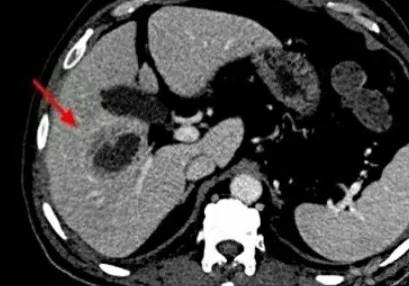

肝脓肿是细菌、真菌或溶组织阿米巴原虫等多种微生物引起的肝脏化脓性病变, 主要分为三个类型,分别是细菌性肝脓肿、真菌性肝脓肿、阿米巴肝脓肿,细菌性肝脓肿是最多的。

肝脓肿